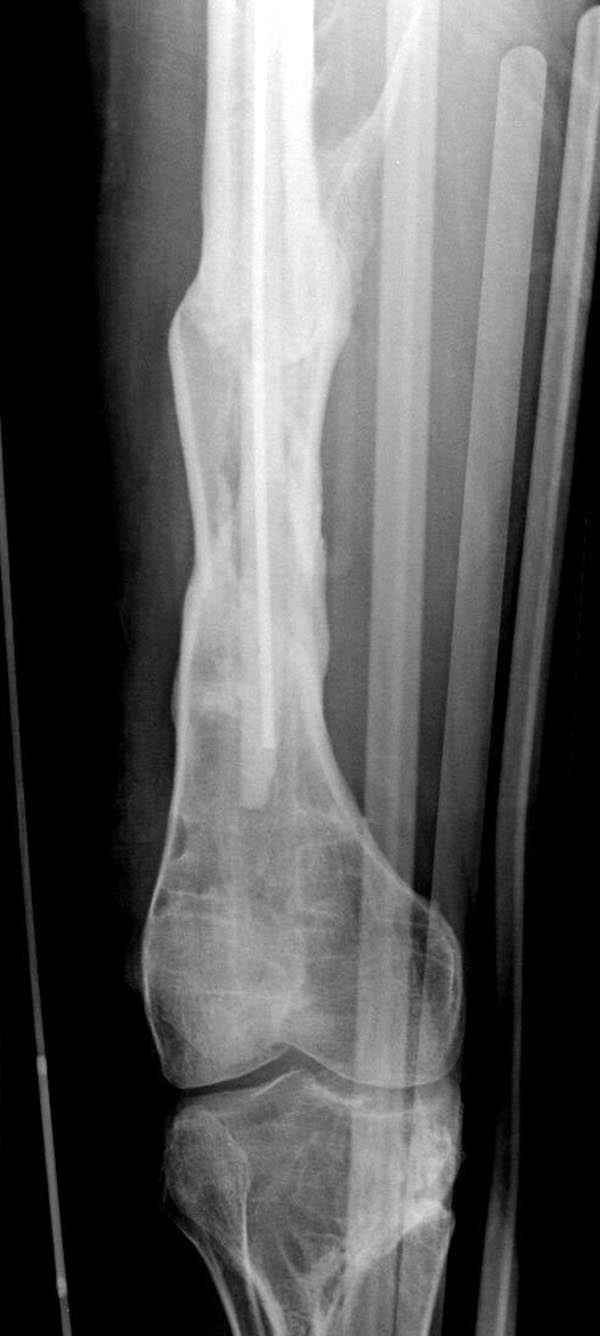

Мы не дождались “Happy End”, у больного IQ в пределах 70%, через 6 месяцев вернулся после небольшой травмы, споткнувшись получил перелом

того же бедра (рис №7).

На следующий день произвели интрамедуллярный остеосинтез: этапы во время операции (рис №8, №9)

и последующих снимках (рис №10, 11, 12, 13) перелом сростается и передвигается с полной нагрузкой.